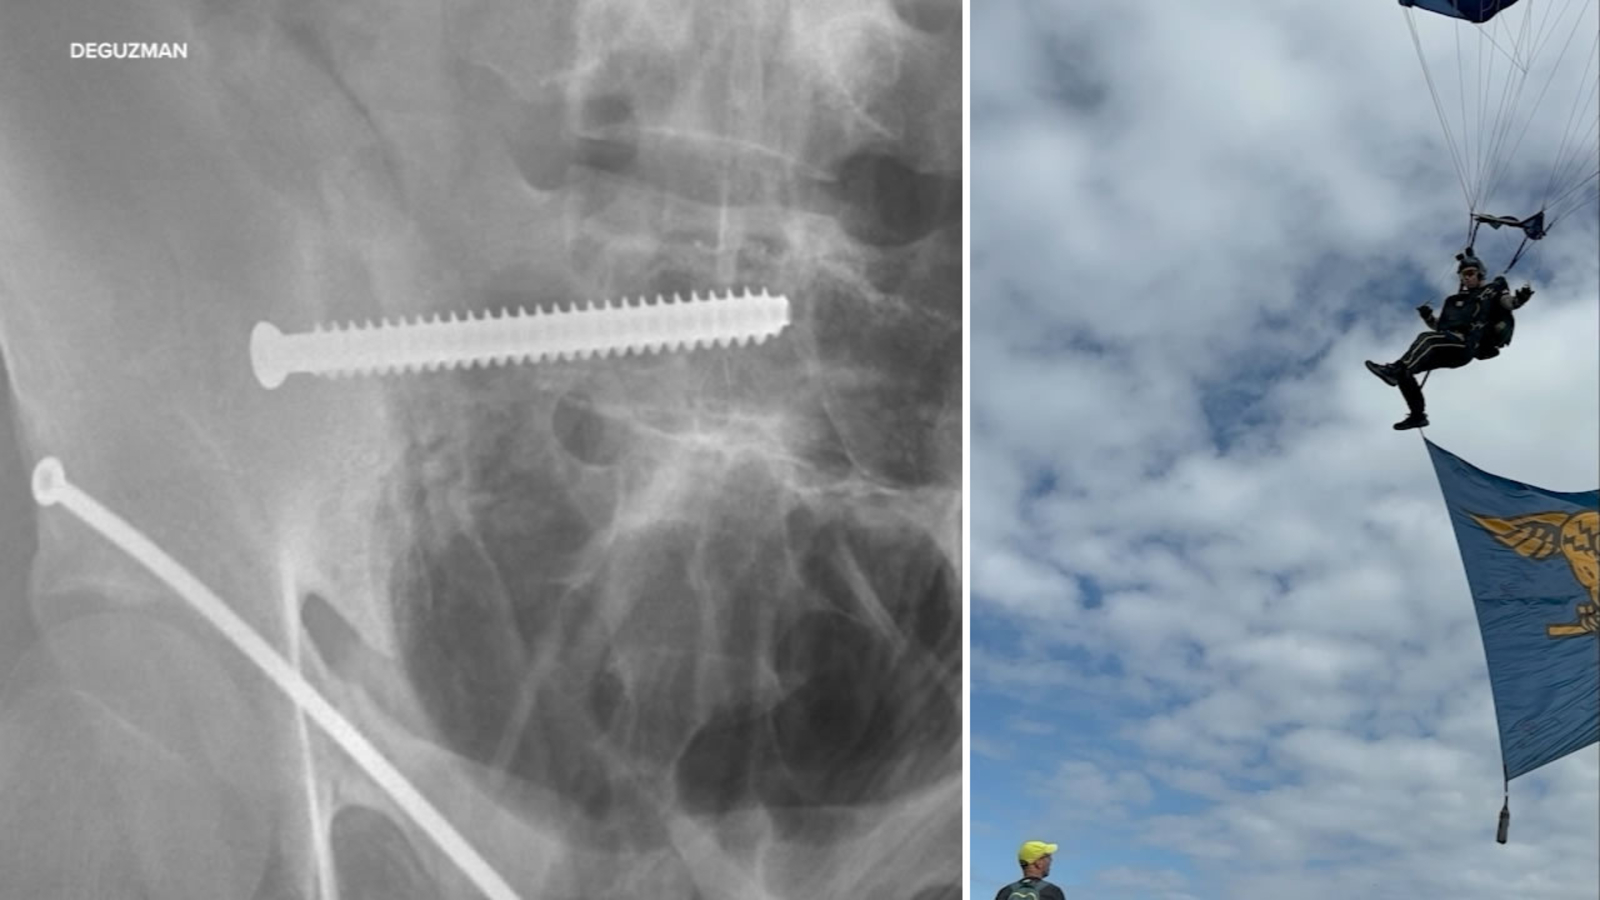

"She sustained pelvic fractures they took her to the hospital. They did surgery. They think the surgery went well - obviously we can't tell yet," said Gomerman. "My initial concern is she going to be able to walk without a limp? Did a growth plate get hit? It sounds like, the hope is that she will be able to walk without a limp and it's not going to impede her growing. Her mom's concern is that will she be able to have kids naturally? The doctors don't know that will be possible unless they take the pins and screws out because it's holding her pelvis in place."